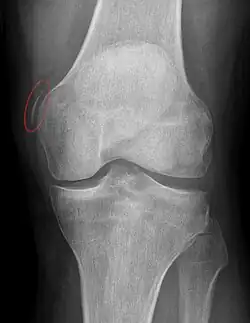

Pellegrini–Stieda syndrome (also called Stieda disease and Köhler–Pellegrini–Stieda disease) is the ossification of the superior part of the medial collateral ligament of the knee. It is a common incidental finding on knee radiographs. It is named for the Italian surgeon A. Pellegrini (b. 1877) and the German surgeon A. Stieda (1869–1945).[1] While the eponym refers to Pellegrini and Stieda, the condition was first discovered by Köhler in 1903, before any namesakes. Pellegrini-Stieda combines the aforementioned radiographic findings and concomitant medial knee joint pain or restricted range of motion.[2]

Diagnosis is typically made on radiographs demonstrating the Pellegrini-Stieda syndrome sign accompanied by pain or restriction of range-of-motion of the knee joint.[2] Pellegrini-Stieda syndrome sign is typically described by a longitudinally linear opacity, which is a process that is describes characteristic of calcification in the soft tissue located medial to the medial femoral condyle.[2] This calcification seen on imaging represents the ossification of the medial collateral ligament, which typically does not develop until approximately three weeks after the initial injury.[2]It is important to note to distinguish this radiographic finding from that of a medial femoral condyle avulsion fracture, which is an injury in which a pulling force of a tendon or ligament fractures away a piece of the bone from its attachment site.[2]

Alternative classification syndrome for Pellegrini-Stieda lesions of Type 1 through Type 4 based on their location:[2]

- Type 1- is referred to as a beak-like appearance and describes the ossification arising from the femur and extending inferiorly in the medial collateral ligament.

- Type 2-is defines a tear-drop pattern, localized within the medial collateral ligament without any attachment to the femur.

- Type 3-presents as an elongated ossification superior to the femur lying in the distal adductor magnus tendon.

- Type 4-is also characterized as a beak-like appearance arising from the femur. However, there are some cases where this ossification extends into both the medial collateral ligament and adductor magnus tendon. In then, the original attribution of the syndrome to the medial collateral ligament may now be outdated as many publications have suggested concomitant and even sometimes preferential involvement of the adductor magnus tendon, medial head of the gastrocnemius, or medial patellofemoral ligament.[2]